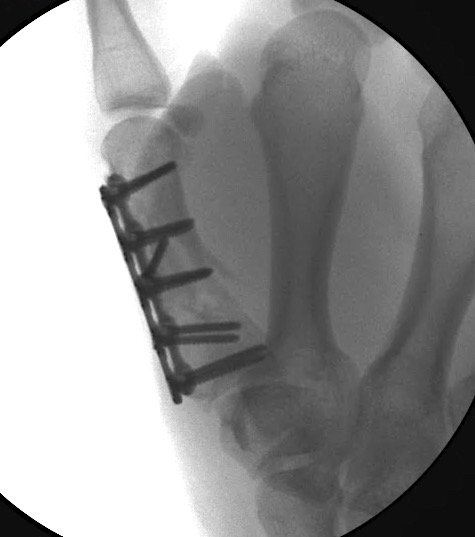

Case 1:

A 64-year-old male suffered a multi-fragmentary fracture of his right thumb metacarpal (Fig 1). An adapted 12-hole strut plate from the variable angle locking hand system was the implant of choice for fixation (Figs 2 - 4).

The strut plate provided good stability in a comminuted extraaricular fracture pattern and enables immediate mobilization. Bone callus formation was not witnessed during the healing process.